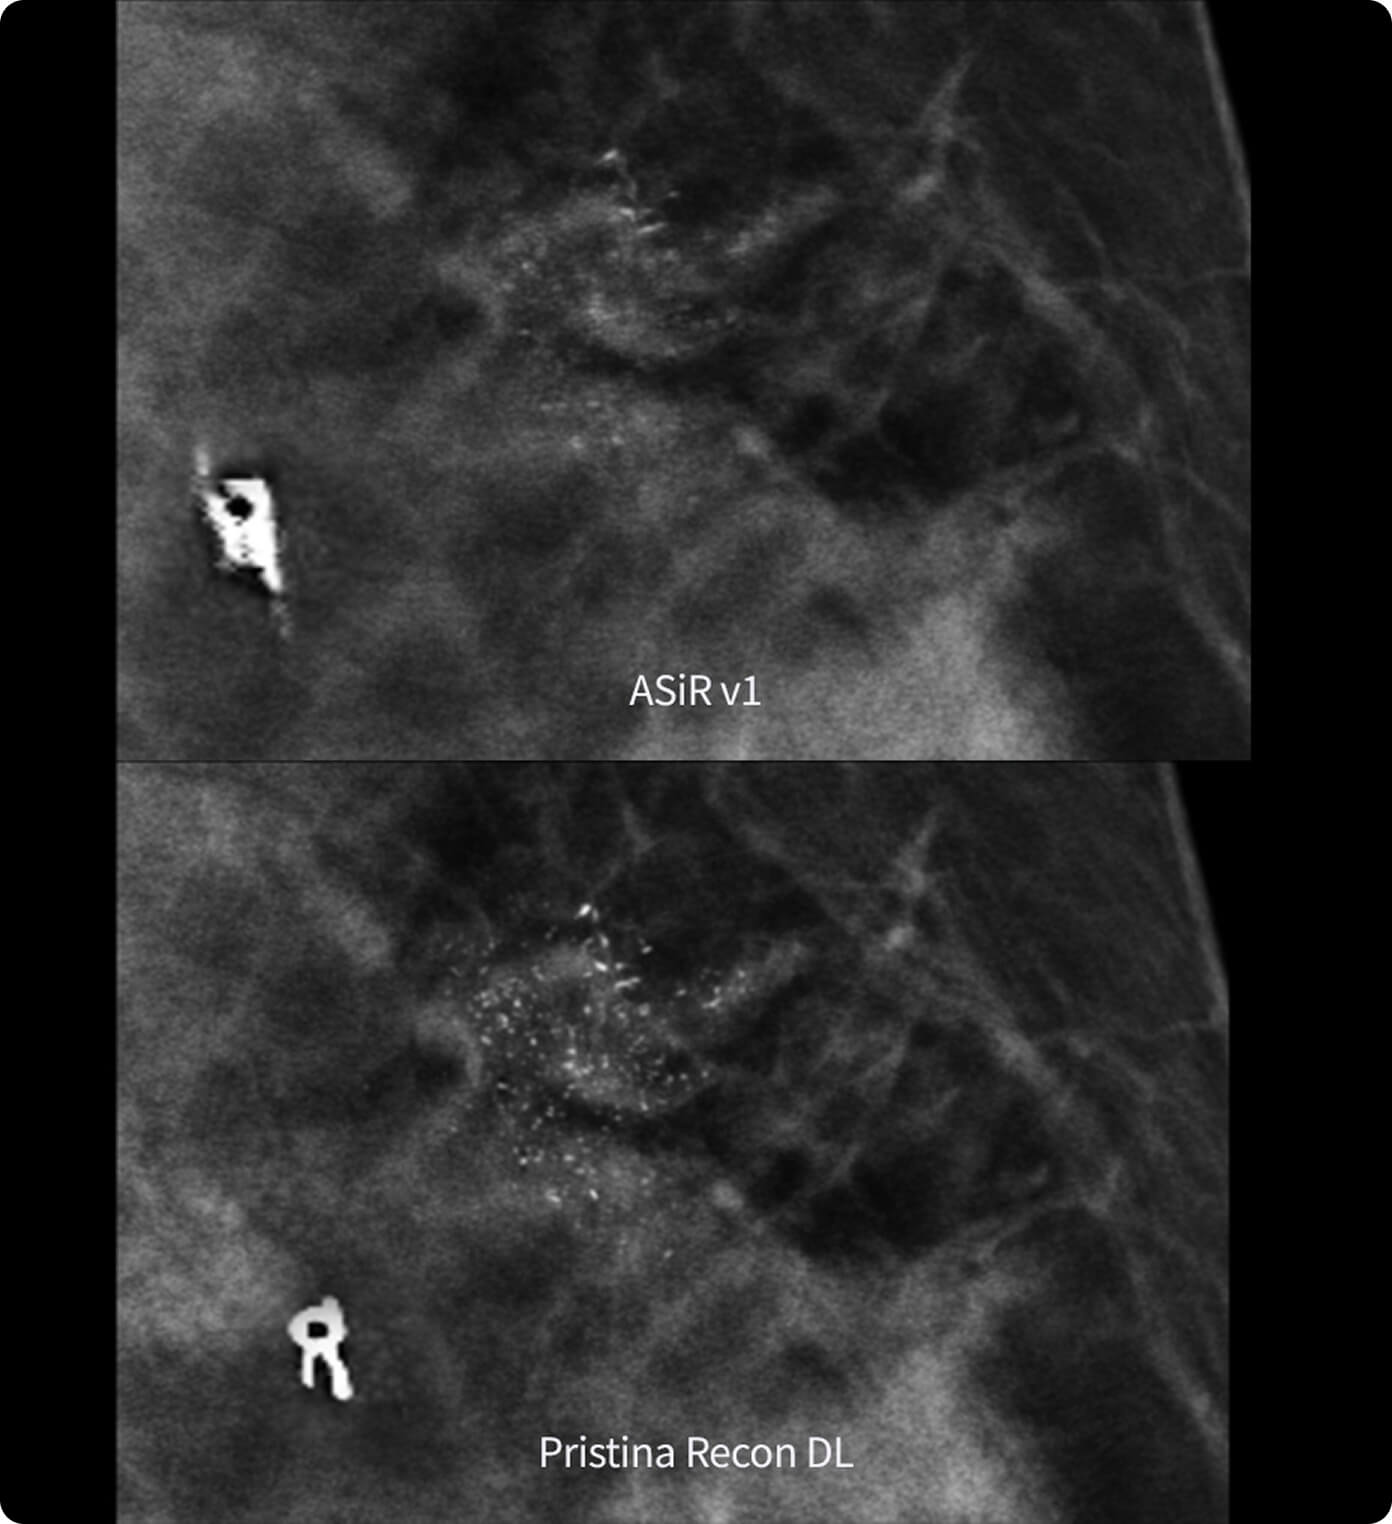

La prima soluzione per la gestione del movimento respiratorio che non include un dispositivo di gating. Monitora attivamente il movimento respiratorio in background di ogni procedura PET/TC. Quando rileva un'anomalia, modifica automaticamente la scansione e integra ciò che apprende nell'immagine finale in tempo reale.

Al termine di una scansione, MotionFree elimina gli artefatti da movimento dalle immagini PET. Integra tutte le correzioni del movimento respiratorio nella ricostruzione finale dell'immagine.